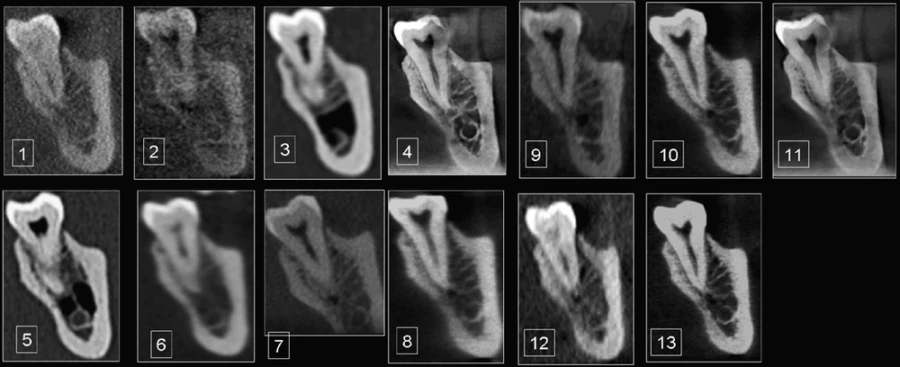

Đọc tiếpTÓM TẮT Mục tiêu Nhằm so sánh chất lượng hình ảnh và khả năng hiển thị các cấu trúc giải…